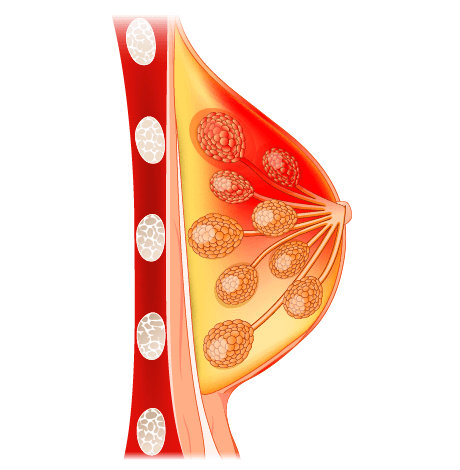

A mastectomy is a high-risk surgical procedure commonly referred to as breast removal surgery and generally aims for cancerous tissue removal either partially or completely from one or both breasts.